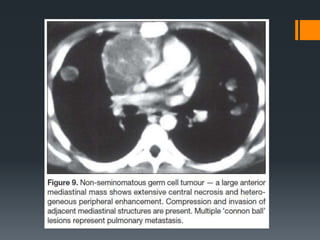

Germ Cell Tumour

Germ-cell tumors are the most common cause of a fat containing lesions in the

anterior mediastinum and the second most common cause of an anterior

mediastinal mass in children.

Approximately 90 % are benign germ-cell tumors.

Most arise in the thymus.

Mediastinal teratoma occurs in children and young adults with no sex

predilection.

On CT, the teratoma appears as a multi-locular cystic tumour with walls of

variable thickness. The combination of fluid, soft tissue, calcium, and fat

attenuation in an anterior mediastinal mass is a highly specific finding that

allows the prospective diagnosis of mature teratoma. Mature teratomas can be

very large and still be benign.

A fat-fluid level produced by high lipid content in the cyst fluid is a rare but

diagnostic sign.